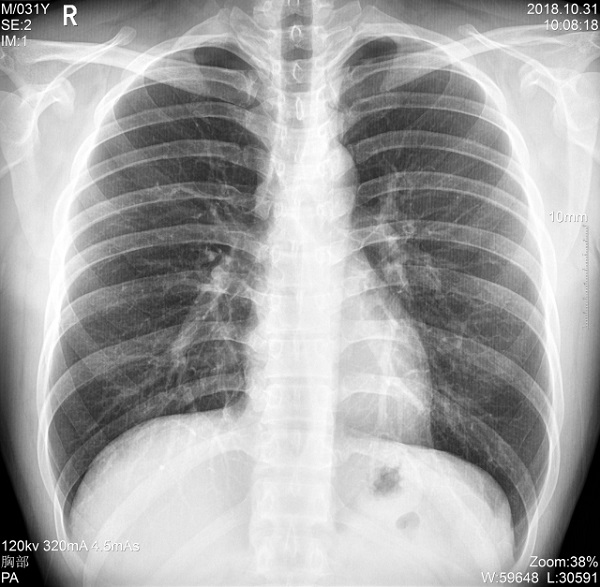

一、肥胖患者、组织较厚部位清晰成像

管电流大小与设备输出X射线的能力相关,管电流越大,设备输出的射线量越充沛。PLX5500的最大管电流达到了710mA,输出的射线能够满足各体型患者的拍摄需求,即便是体重达上百公斤的患者,也能够获得清晰的图像。